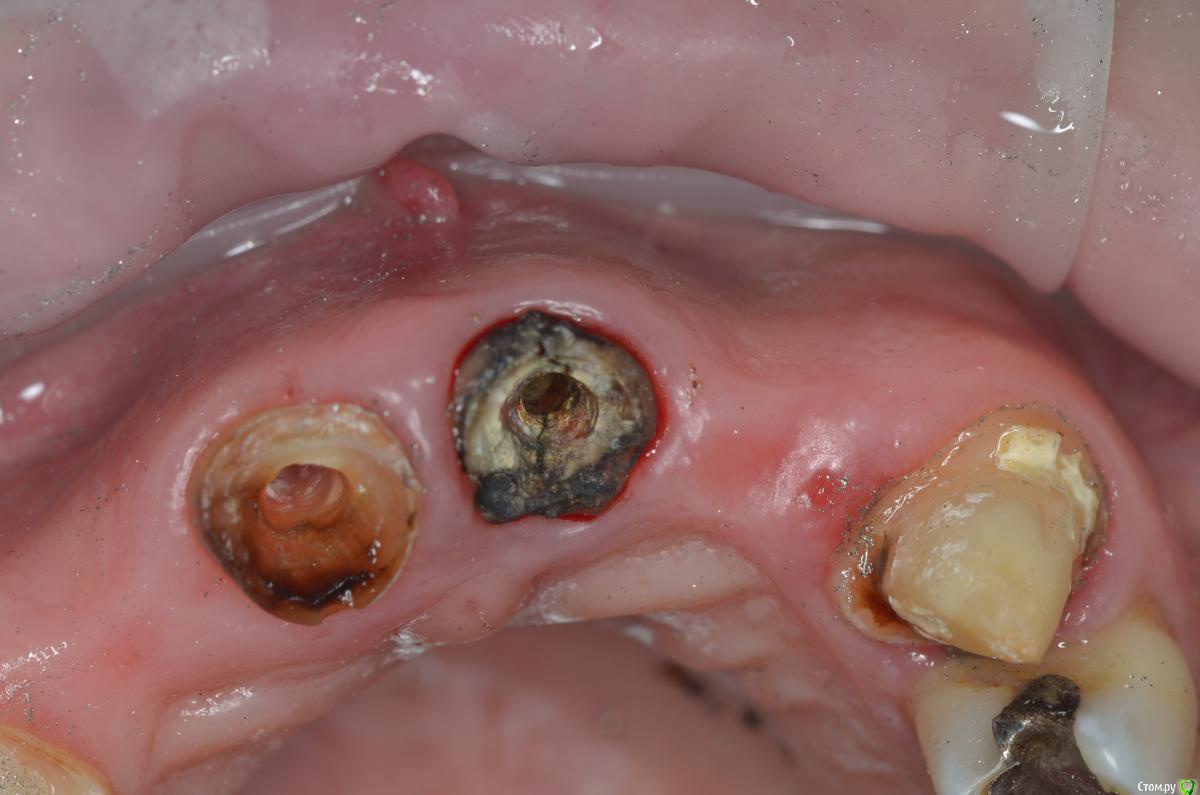

gangsta85 Опубликовано 27 сентября, 2016 Поделиться Опубликовано 27 сентября, 2016 Здравствуйте, уважаемые коллеги.Помогите пожалуйста разобраться.Центральные резцы в\ч были удалены и установлено 2 имплантата с пластикой десны, 12,22 отсутствуют в области 12 трансплантация слизистого лоскута.В тот же день изготовлены времянки по ключу с ваксапа. профиль трансгингивальной части сделан максимально под размер постоянной реставрации. 12,22 овоиды плотно прилегающие к десне.Вопросы:- Можно ли изготовить времянки сразу по форме максимально похожей на будущие реставраций и свести к минимуму коррекции профиля десны?- можно ли сделать надрез в области 22 и максимально погрузить в десну овоид 22, насколько плотно можно прижать овоид 11 в области слизистого трансплантата?- можно ли в такой ситуации добиться формирования десневых сосочков в области 12,22?-через какое время можно снять времянки для коррекции?- постоянная реставрация через 4 месяца? Что если снять слепок в день операции в лаборатории отфрезеровать времянки и установить через 1-2 дня , удастся ли в программе отмоделировать правильный профиль десны и овоиды? Как бы вы предпочли сделать времянки на CAD\CAM или в ручную? Ссылка на комментарий